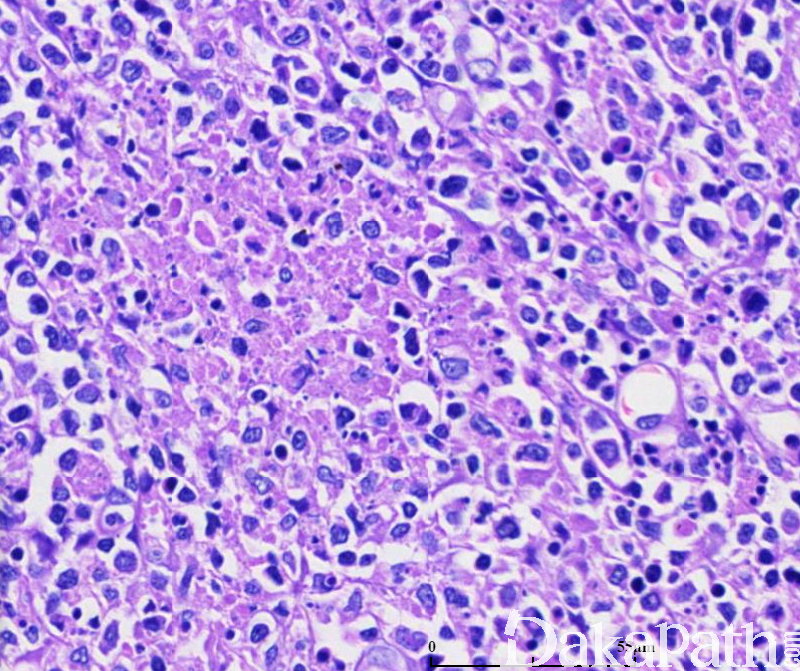

受累淋巴结为灶状、界限清楚的副皮质区坏死性病变,其中见大量的核碎片、散在纤维素沉积和单核细胞聚集,并见大量浆细胞样树突细胞和活化的 T 细胞,浆细胞和中性粒细胞非常少。

增殖型:副皮质区多量免疫母细胞增生,夹杂大的组织细胞、成片的浆细胞样树突细胞及核碎裂小体,组织细胞部分核有切迹、扭曲,及新月型组织细胞(细胞核偏位、弯月形、胞质丰富,内可含核碎片)。

坏死型:为最常见组织学类型。表现为副皮质区不含中性粒细胞浸润的片状坏死,有大量的被单个核细胞围绕的核碎裂碎片,核碎裂碎片可位于组织细胞外或被组织细胞吞噬。

黄色瘤型:此型最少见,可能代表本病的愈合期。可伴有或不伴有坏死,含有大量泡沫状组织细胞,免疫母细胞比其他亚型少。